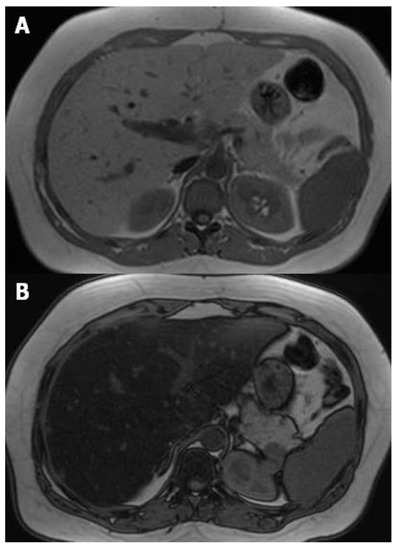

Proton density fat fraction (PDFF) measurement by MRI appears to be the most objective test for the quantification of liver steatosis, and has been recently adopted as a standard reference in clinical trials [17,18]. This technique overcomes the limits of dual-echo sequence, such as the T2* effect, T1 bias, spectral complexity of fat, eddy currents, noise bias, and magnetic non-homogeneity. PDFF is the ratio of density of mobile lipid protons (primarily triglycerides) and the total density of protons from water and fat. Moreover, it shows objective fat quantification and grading similar to magnetic resonance spectroscopy (MRS) in a single breath-hold, and measurement is easily performed by drawing a region of interest (ROI) on an automated PDFF map (Figure 4) [19].

Figure 4.

(A,B) Images from datasets acquired from a multi-echo, low flip angle sequence with clear separation of fat from nonfat tissue; (C) the R2 image is useful in the evaluation of iron concentration; (D) the fat-fraction image allows one to easily obtain the fat percentage by drawing a region of interest (ROI) within the parenchyma.

Above all, it is very easy and practical for fat fraction measurement. In pediatric patients, comparison of biopsy and PDFF has shown promising results [20]. PDFF is an unconfounded and fundamental property of tissue, and it is insensitive to changes in acquisition parameters, thereby making it a robust quantitative biomarker [21]. PDFF is uniform across scanner platform and manufacturer and even field strength, and can standardize MRI-based fat quantification [22,23]. Moreover, simultaneous calculation of R2* and T2* maps from the same MRI sequence enables the estimation of hepatic iron content, which can be important for the diagnosis of co-existing fatty liver and hepatic iron overload [24,25].